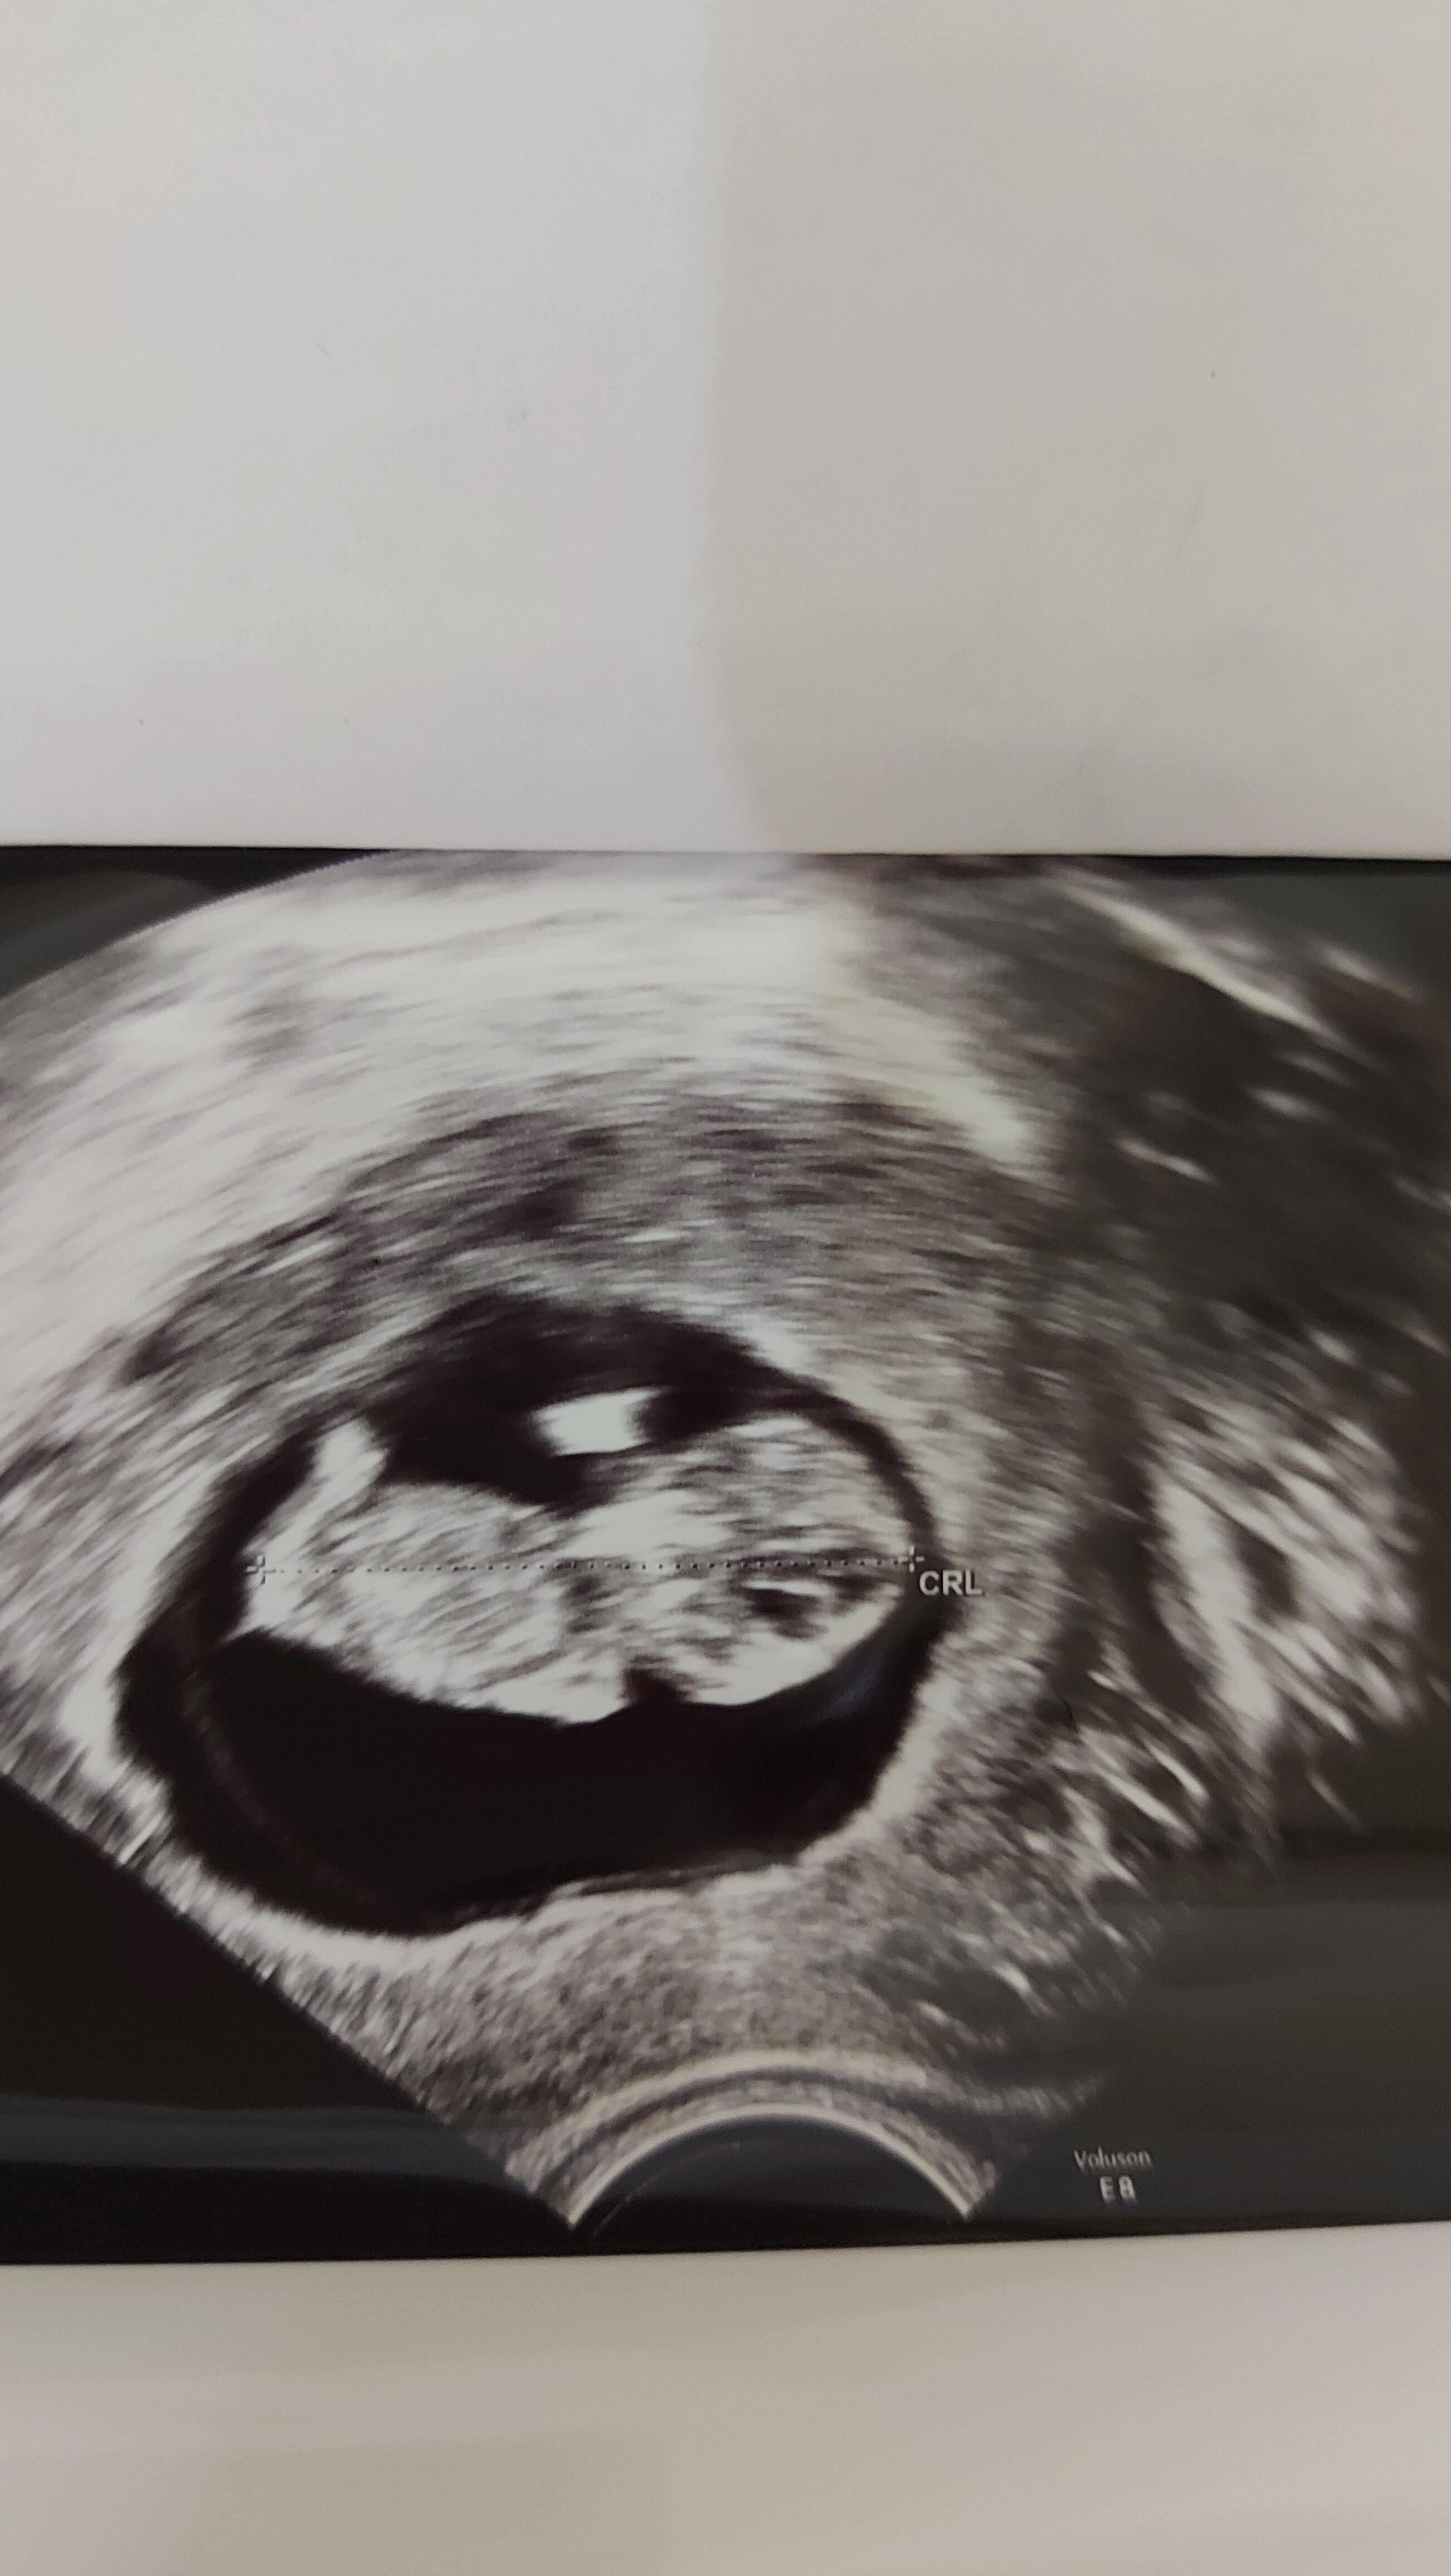

16.08 – wizyta @Orchidea33